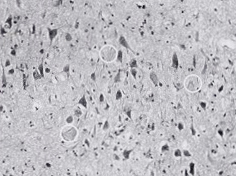

動脈硬化が軽かったことは、脳にもよい影響がありました。ぎんさんは、脳の血管も非常にきれいで、アルツハイマーにみられる神経細胞の変化が少しありま したが、動脈硬化による脳の変化はありませんでした。ふつう一〇〇歳以上になると、脳のなかで痴呆の病変が合併することが多く、痴呆の程度も重くなるとさ れています。ぎんさんは一〇五歳ころまで痴呆がなくカクシャクとしておられましたが、それは動脈硬化の軽さと関係が深かったのです。

| 脳の動脈(矢印)やはり柔らかい血管で、脳梗塞などはありませんでした | 脳を顕微鏡でみたところ 変性しているアルツハイマーの像(○印)がみられましたが、動脈硬化による脳の変化はありません |